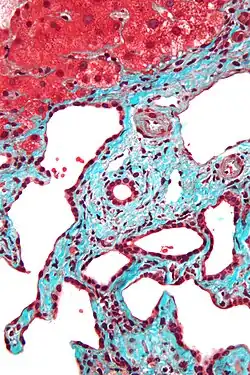

Micrograph of a bile duct hamartoma. Trichrome stain. Intermediate magnification -